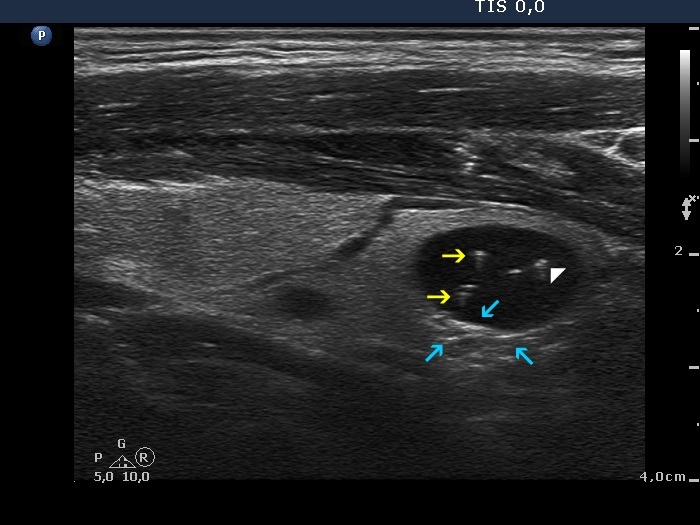

There are several unambiguous figures with typical presentation (yellow arrows), while several hyperechogenic granules lack dorsal acoustic shadow (white double arrows) which theoretically might be punctate echogenic foci. On the other hand, in the presence of typical comet-tail artifacts, similarly bright non-typical forms more likely belong to the same category. Moreover, punctate echogenic foci (microcalcifications) cannot be found in cystic fluid.